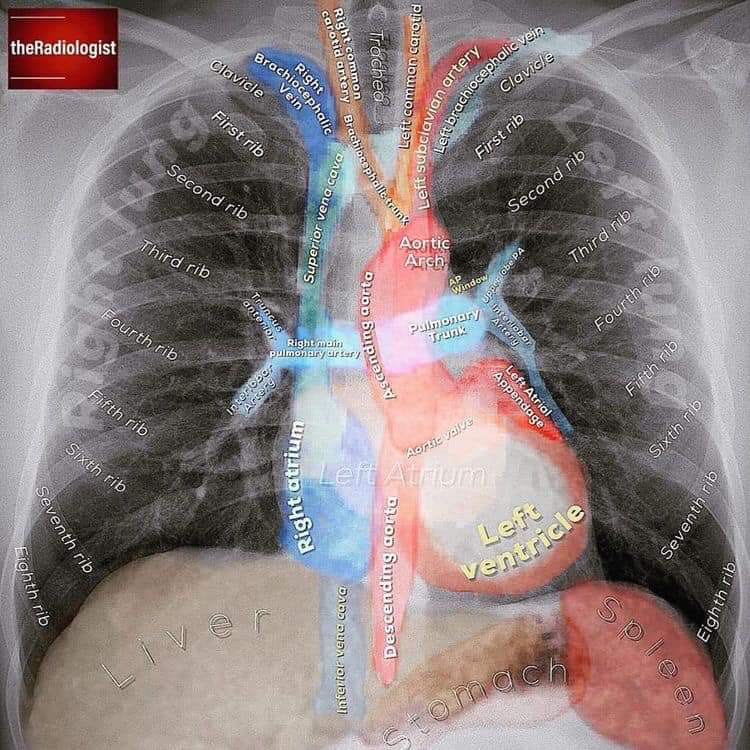

Chest xrays, like ECGs, can be difficult to interpret. Medics for some reason bend over backwards to pretend to each other that they are easy when they are not. This beautifully clear "xray atlas" is very helpful!I wish I had seen this as a medical student..https://twitter.com/ccpractitioner/status/1218823371821023232 …